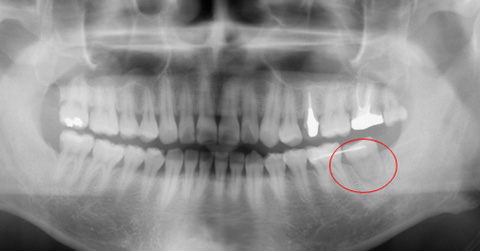

![]() |

| 移植直後(赤丸)のレントゲン像 |